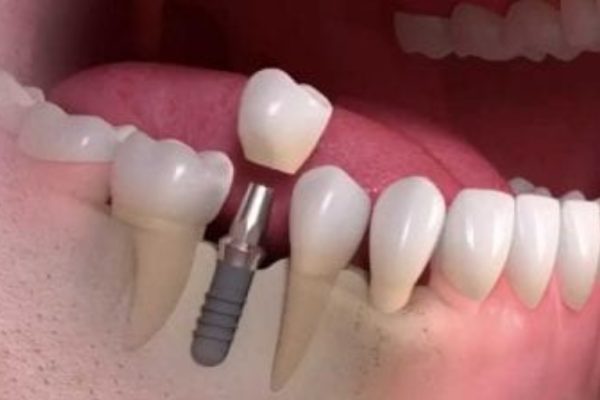

Segunda Cirugía

(Pilar y Toma de Impresión):

Conexión del pilar:

– Después de curarse de la primera cirugía, haga otra incisión en las encías.

– Confirme la integración exitosa del dispositivo en la mandíbula.

– Si está bien integrado, conecte el pilar al dispositivo, sobresaliendo por encima de las encías.Toma de impresiones:

Fabricación y fijación de coronas:

- Opcionalmente, coloque una corona temporal antes de fabricarla en el laboratorio dental.

- Una vez fabricada la corona (tarda aproximadamente una semana), coloque la corona final en el pilar.

- Con ello, el diente implantado queda totalmente restaurado, permitiendo al paciente tener una sonrisa normal.